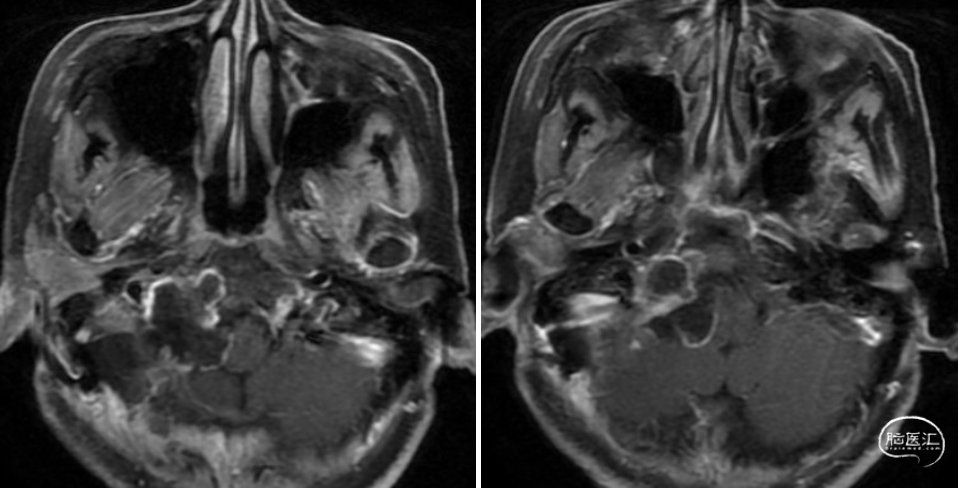

术前影像

该例患者CT提示颈静脉孔及舌下神经管扩张,结合病史及查体,考虑诊断为舌下神经鞘瘤,病变主体位于颈静脉孔区及舌下神经管区,部分突入颅内,未侵犯颈部,故术中无需过多暴露颈部,只需乙状窦后方开颅,磨除骨质开放颈静脉孔及舌下神经管即可暴露肿瘤,手术切口采用耳后直切口即可满足暴露。